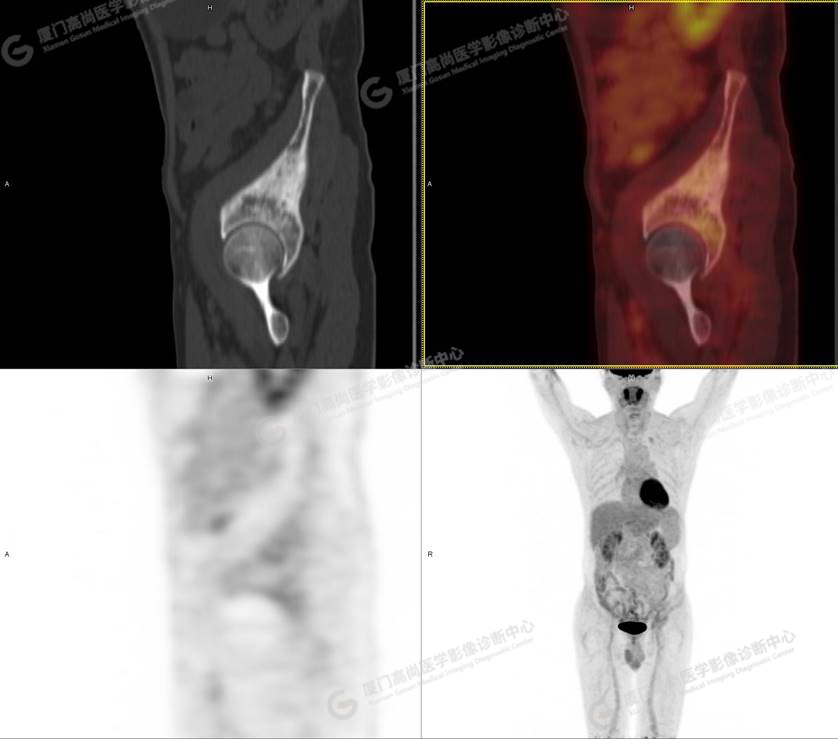

PET/CT影像圖

圖1

圖2

圖3

圖4

PET/CT所見:左側(cè)髂骨、髖臼及恥骨骨質(zhì)密度不均勻增高,CT值約594Hu,邊緣模糊,放射性攝取輕度增高,SUVmax 2.79,周圍軟組織未見明顯異常。